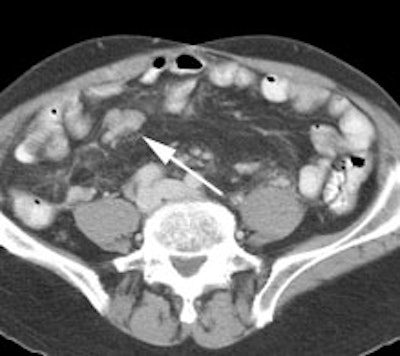

Recurrent colorectal cancer: The patient shown below had a history of colon cancer and a rising CEA level. FDG PET exam revealed a site of tracer uptake in the mesentery (black arrows) which corresponded to an enlarged lymph node seen retrospectively on CT scan (white arrow). |

|